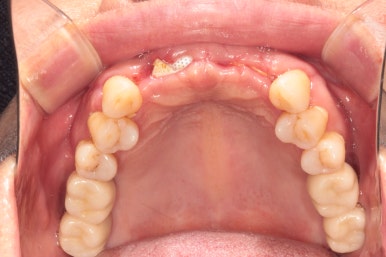

50대 여자 환자분입니다. 처음에 내원하셨을 때 정면 사진이에요.

딱 보아도 잇몸 상태가 참 좋지 않았습니다. ㅠㅠ 특히 위 앞니는 가만히 있어도 고름이 나오고 있는 상태지요..

만성치주염을 갖고 계신 환자분들은 이러한 상황을 조심하셔야 합니다.. 너무 방치되면 정말 임플란트를 심을 잇몸뼈가 하나도 남지 않을 수 있어요.... 그러다 진짜 틀니 하셔야 합니다!!...